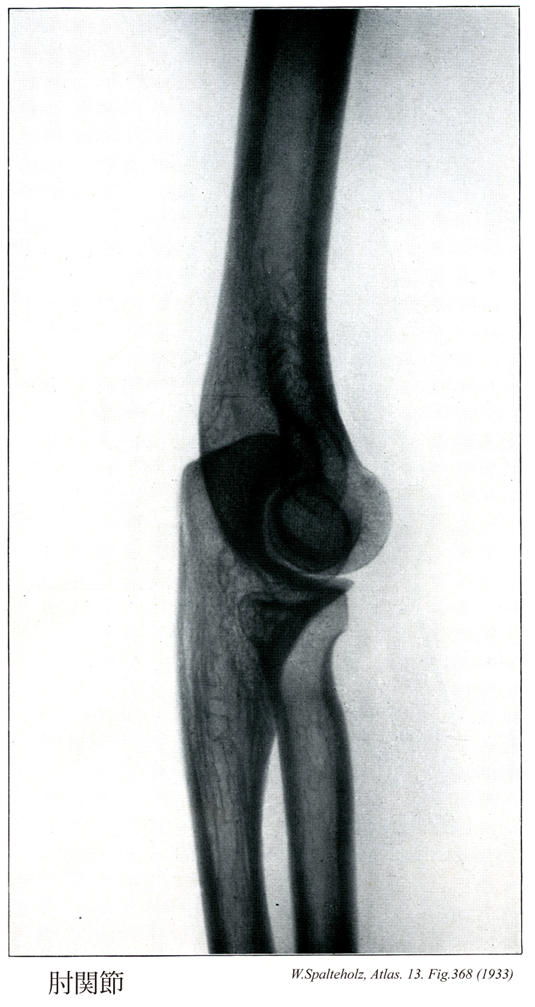

368_00【Elbow joint肘関節 Articulatio cubiti】 Joint formed by the humerus, radius, and ulna.

→(肘関節は上腕骨と橈骨、尺骨の3骨の間に生じた複関節で、肘の屈伸を行う。したがって分類状は1軸性の蝶番関節とみることができる。上腕骨滑車と尺骨の滑車切痕との間の腕尺関節、上腕骨小頭と橈骨頭との間の腕橈切痕との間の上頭尺関節が共通の関節包におおわれる。しかし後者は機能的には下橈尺関節とともに前腕の回旋に関係するので、前2者とは別に記載するのが通例である。上腕骨の内側および外側上顆は関節包におおわれない。関節包の内側と外側はそれぞれ内側側副靱帯および外側側副靱帯によって補強される。橈骨輪状靱帯は、関節包の内面が肥厚した幅約1cmの靱帯で、尺骨の橈骨切痕の前縁からおこり、橈骨の関節環状面を輪状にとりまいたのち、再び尺骨の橈骨切痕の後縁につく。この靱帯の関節腔に面した部分は軟骨性となり、尺骨の橈骨切痕とともに上橈尺関節における関節窩を形成する。肘関節における屈伸運動の役割を演ずるのは腕尺関節である。しかし上腕骨滑車の内側部の直径が外側部のそれよりやや大きいため、肘を伸ばすと、その時の尺骨の長軸は、上腕骨長軸よりも外方へ約10~20°の傾きを示す。この角をcarrying angleという。しかし肘を曲げたときは、両骨の長軸は重なり合う。)